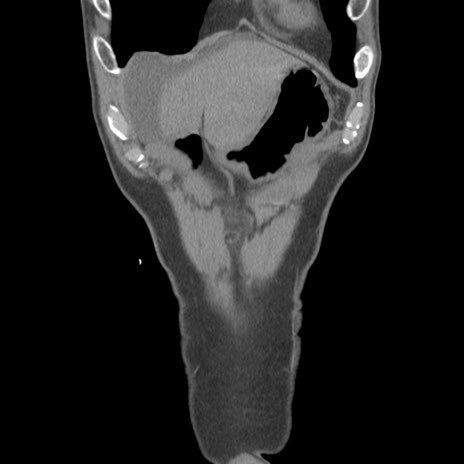

症例56 CT(冠状断像)

横断像